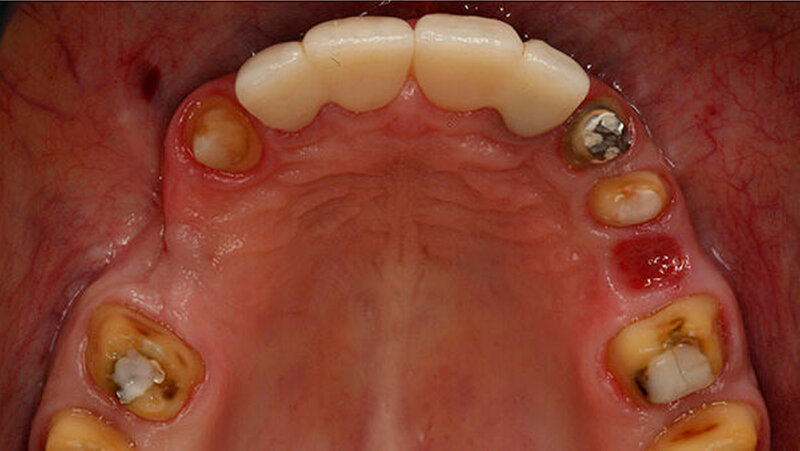

Beispiele für individuellen ZE

Die Jahrestagung der Deutschen Gesellschaft für Prothetische Zahnmedizin und Biomaterialien (PGPro) in Ulm geht der Frage nach, welche Versorgungskonzepte - mit guten Langzeitergebnissen - individuell und preiswert machbar sind. Gute Beispiele finden Sie in unserer Bilderstrecke!